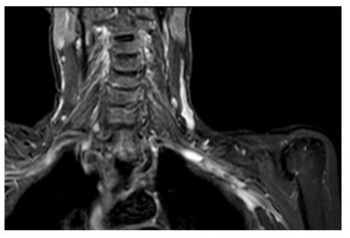

Figure 1B: STIR MRI coronal plane: hypersignal of the wall of the right subclavian artery.